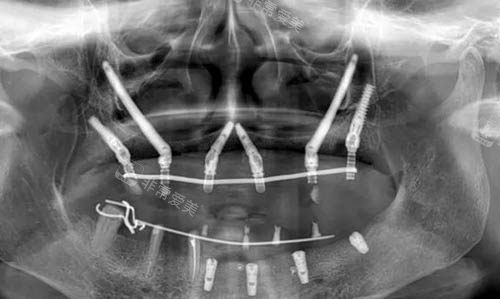

穿颧穿翼种植ct照片

针对骨量不足、牙槽骨萎缩等疑难病例,医院采用国内比较靠前的穿颧穿翼种植技术,实现即刻负重种植,避免传统植骨手术的漫长改善期。

该技术尤其适合半口或全口无牙患者,种植体稳定性强,术后咀嚼功能改善显著。

穿颧穿翼种植分区图解